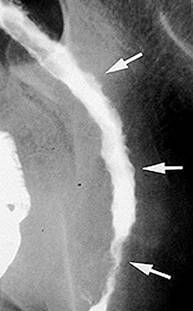

Examenul radiologic cu dublu contrast apreciaza distensibilitatea colonului. Initial se evidentiaza aspectul neregulat, fin granular al mucoasei, scaderea distensibilitatii colonului si dehaustrarea. Ulterior apar ulceratiile ce dau pe imaginea de profil aspectul de spiculi marginali si imagini de aditie, iar pe cea de fata pete opace suspendate. In stadiile avansate apar ulceratiile "in buton de camasa". Examenul radiologic cu substana de contrast este contraindicat in RCUH severa/fulminanta, avand risc de precipitare a megacolonului toxic.

Colita ulcerativa -puseu de activitate- Colita ulcerativa cronica-dehaustrarea

ulceratii si inflamatia extensiva sigmoidului

a mucoasei